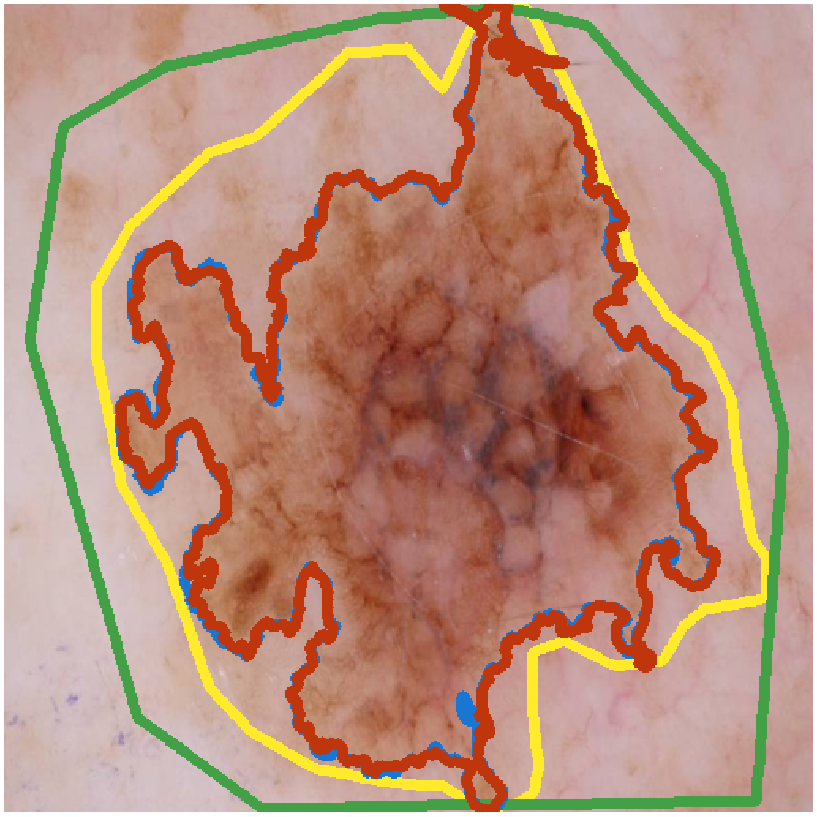

What Can We Learn from Inter-Annotator Variability in Skin Lesion Segmentation?

Kumar Abhishek, Jeremy Kawahara, Ghassan Hamarneh

Medical Image Computing and Computer-Assisted Intervention (MICCAI) ISIC Skin Image Analysis Workshop (MICCAI ISIC), 2025

(Best Paper Award | SFU FAS 3MT Runner-Up | SFU 3MT Finalist | Invited 3MT at University Women's Club of Vancouver)

We show a statistically significant association between inter-annotator agreement (IAA) and the malignancy of skin lesions, and leverage this association to improve lesion diagnosis performance. [Abstract] [BibTeX] [Presentation Slides]

Medical image segmentation exhibits intra- and inter-annotator variability due to ambiguous object boundaries, annotator preferences, expertise, and tools, among other factors. Lesions with ambiguous boundaries, e.g., spiculated or infiltrative nodules, or irregular borders per the ABCD rule, are particularly prone to disagreement and are often associated with malignancy. In this work, we curate IMA++, the largest multi-annotator skin lesion segmentation dataset, on which we conduct an in-depth study of variability due to annotator, malignancy, tool, and skill factors. We find a statistically significant (p < 0.001) association between inter-annotator agreement (IAA), measured using Dice, and the malignancy of skin lesions. We further show that IAA can be accurately predicted directly from dermoscopic images, achieving a mean absolute error of 0.108. Finally, we leverage this association by utilizing IAA as a “soft” clinical feature within a multi-task learning objective, yielding a 4.2% improvement in balanced accuracy averaged across multiple model architectures and across IMA++ and four public dermoscopic datasets. The code is available on GitHub.

Segmentation Style Discovery: Application to Skin Lesion Images

Kumar Abhishek, Jeremy Kawahara, Ghassan Hamarneh

Medical Image Computing and Computer-Assisted Intervention (MICCAI) ISIC Skin Image Analysis Workshop (MICCAI ISIC), 2024

(Best Paper Award)

StyleSeg learns plausible, diverse, and semantically consistent segmentation styles without annotator correspondence, outperforming competing methods while maintaining alignment with annotator preferences. [Abstract] [BibTeX] [Presentation Slides]

Variability in medical image segmentation, arising from annotator preferences, expertise, and their choice of tools, has been well documented. While the majority of multi-annotator segmentation approaches focus on modeling annotator-specific preferences, they require annotator-segmentation correspondence. In this work, we introduce the problem of segmentation style discovery, and propose StyleSeg, a segmentation method that learns plausible, diverse, and semantically consistent segmentation styles from a corpus of image-mask pairs without any knowledge of annotator correspondence. StyleSeg consistently outperforms competing methods on four publicly available skin lesion segmentation (SLS) datasets. We also curate ISIC-MultiAnnot, the largest multi-annotator SLS dataset with annotator correspondence, and our results show a strong alignment, using our newly proposed measure AS2, between the predicted styles and annotator preferences. The code and the dataset are available on GitHub.

D-LEMA: Deep Learning Ensembles from Multiple Annotations -- Application to Skin Lesion Segmentation

Zahra Mirikharaji, Kumar Abhishek, Saeed Izadi, Ghassan Hamarneh

ISIC Skin Image Analysis Workshop, IEEE International Conference on Computer Vision and Pattern Recognition (CVPR), 2021

(Best Paper Award)

We propose an ensemble of Bayesian FCNs to perform segmentation from multiple (contradictory) annotations and fuse predictions from multiple base models to improve confidence calibration. [Abstract] [BibTeX] [Presentation Slides]

Medical image segmentation annotations suffer from inter/intra-observer variations even among experts due to intrinsic differences in human annotators and ambiguous boundaries. Leveraging a collection of annotators' opinions for an image is an interesting way of estimating a gold standard. Although training deep models in a supervised setting with a single annotation per image has been extensively studied, generalizing their training to work with data sets containing multiple annotations per image remains a fairly unexplored problem. In this paper, we propose an approach to handle annotators' disagreements when training a deep model. To this end, we propose an ensemble of Bayesian fully convolutional networks (FCNs) for the segmentation task by considering two major factors in the aggregation of multiple ground truth annotations: (1) handling contradictory annotations in the training data originating from inter-annotator disagreements and (2) improving confidence calibration through the fusion of base models predictions. We demonstrate the superior performance of our approach on the ISIC Archive and explore the generalization performance of our proposed method by cross-dataset evaluation on the PH2 and DermoFit data sets.